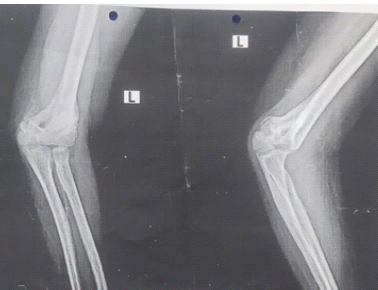

Acute Forearm Compartment Syndrome in a Toddler Caused by Hematoma without Fracture: A Case Report

Yasushi Naganuma , Hiroshi Satake , Norio Fukuda , Michiaki Takagi

………………………………p.121-124